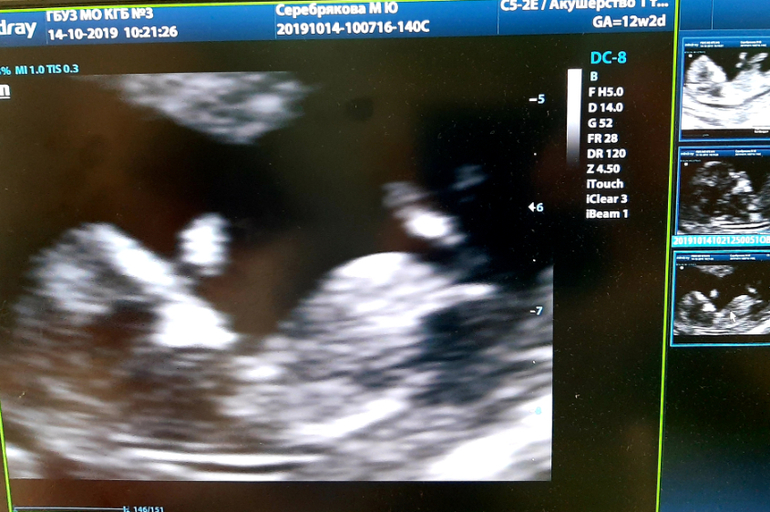

Первый скрининг

Сегодня ходила на скрининг и сдавала кровь в ЖК. Все хорошо, без откланений и соответствует срокам ))) . 11недель и 5 дней. Вмзможный пол сказали, скорее всего бвдет девочка. Мужу я еще не говорила , когда на 2 триместре точно скажут устрою сюрприз, сейчас это стало популярным, ну типа торт резать , шарик лопать или дым запускать в цвет пола)))